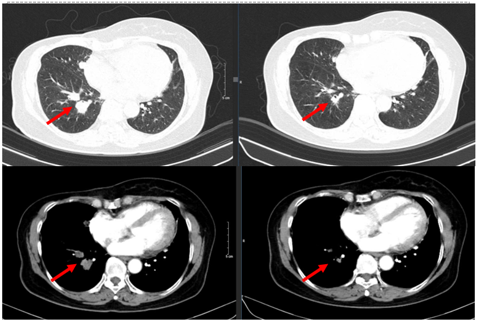

- Chụp cắt lớp vi tính ngực:

+ Thành ngực phải có nốt đặc kích thước khoảng 11x9mm – theo dõi tổn thương tái phát

+ Phổi phải: nhu mô thuỳ giữa và dưới có các khối – nốt đặc, lớn nhất 19x18mm

+ Phổi trái: nhu mô thuỳ trên và đáy phổi sát màng phổi có các khối nốt đặc, lớn nhất 16x17mm

Hình 1. Hình ảnh chụp CT ngực trước điều trị: Tổn thương tái phát thành ngực

Hình 2. Hình ảnh chụp CT ngực trước điều trị: Tổn thương phổi 2 bên